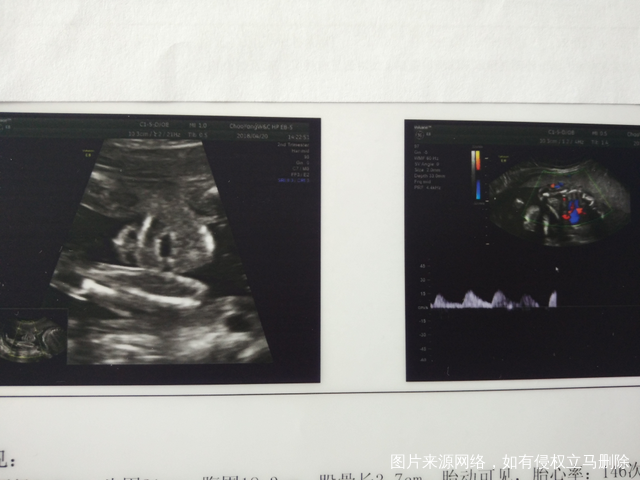

建议胎儿超声心动检查是心脏有什么问题吗?

麻烦医生帮我看下排畸b超